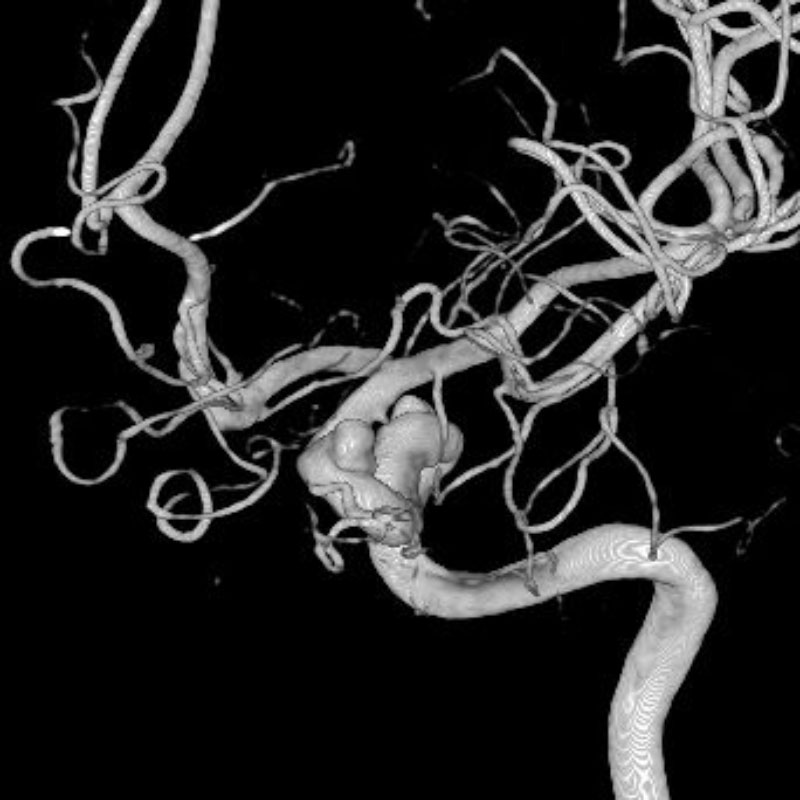

脳動静脈奇形

血管塞栓術

松田/濵田/元永